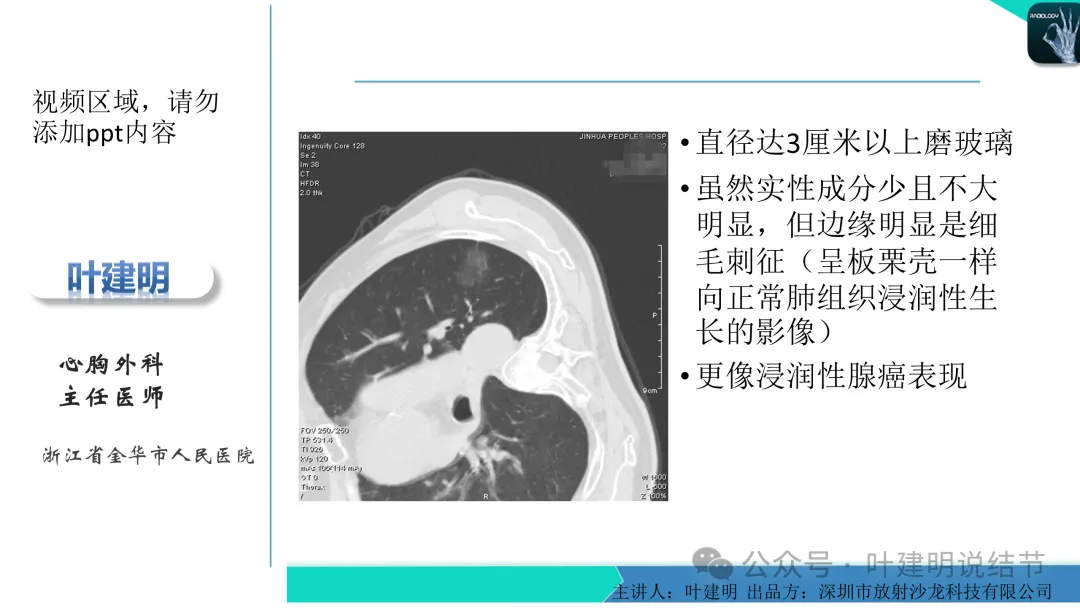

早在2020年时,我受邀在《放射沙龙》做过一个系列的精品课,当时专门总结分析过各类良恶性肺结节与肿块的影像特征,这是当时关于微浸润性腺癌影像特征的分析,今天看来仍基本不太需要改变,大家有兴趣的可以参考: